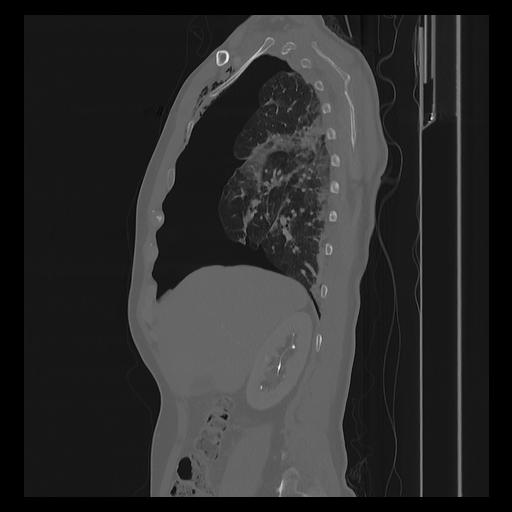

33 PULMON,CE,Sagittal,3.000,PULMON,Sagittal,